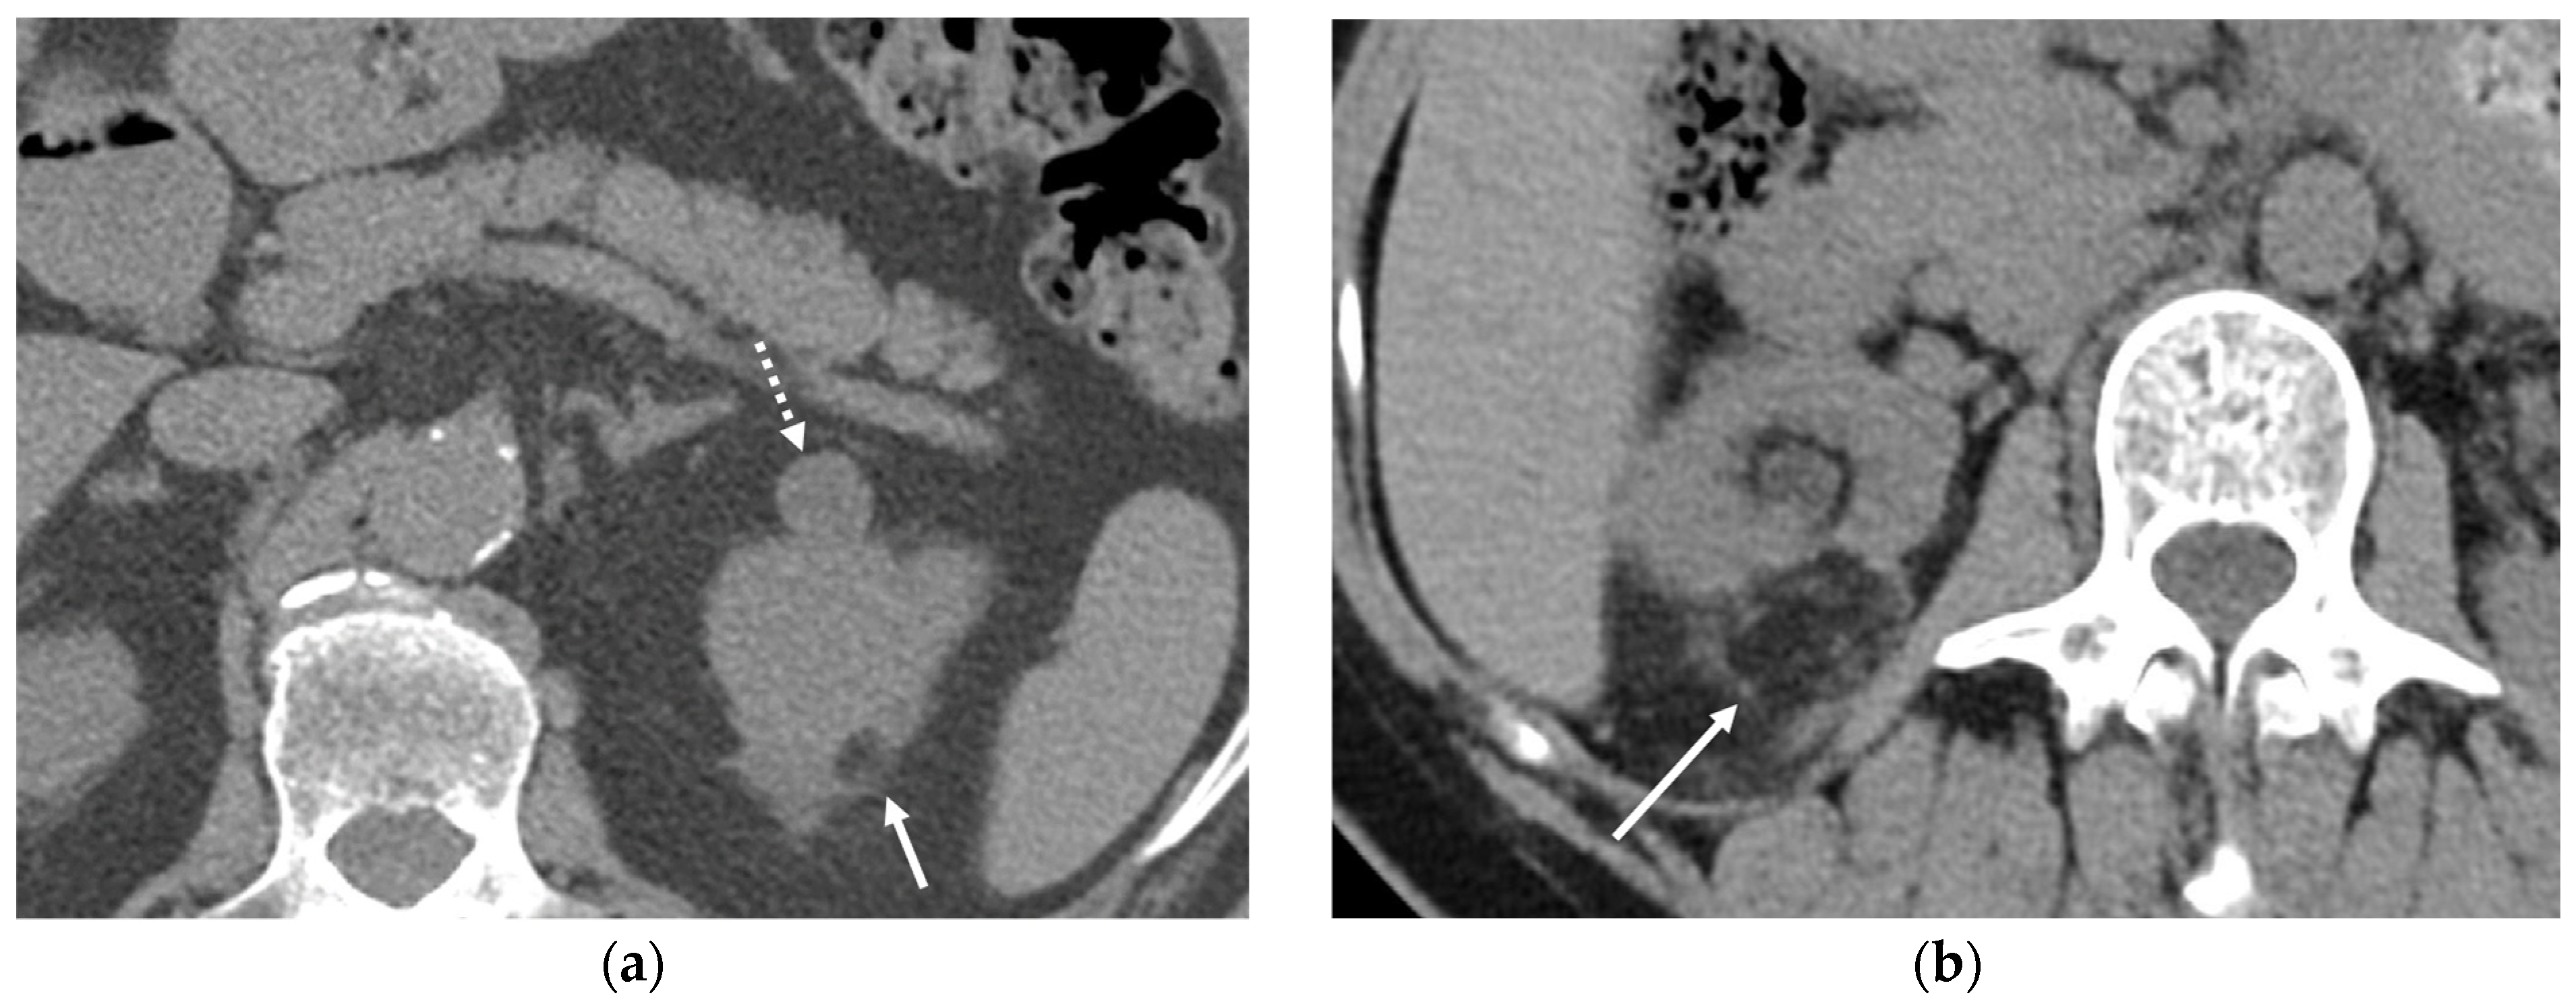

5.3.4. Pancreas